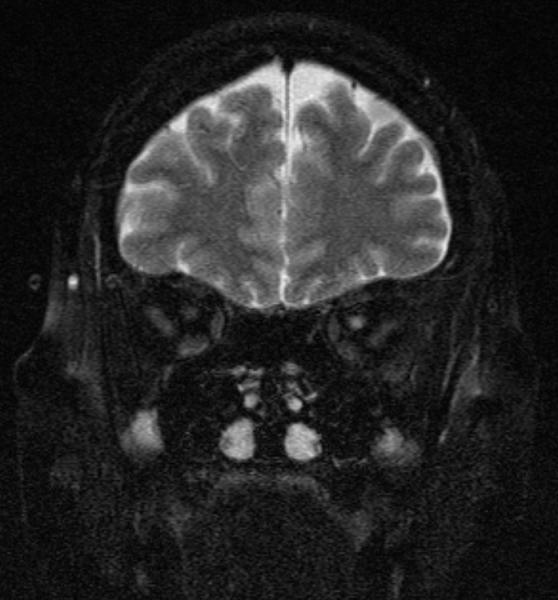

optic_neuritis.jpg